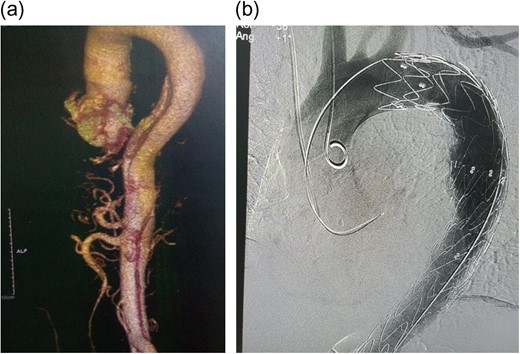

The patient was selected for TEVAR according to Cooper's [5] proposed algorithm and the decision reinforced by the history of non-compliance to medical therapy. A Valiant Captiva (Medtronic) 38 × 200 mm stent was deployed through the right femoral artery into the aorta, landing proximally just distal to the left subclavian artery and distally just distal to the celiac artery with an overlap of 110 mm and effective occlusion of the false lumen (Fig. 1b). Of note, 12 h post-TEVAR however; the patient started complaining of colicky, non-specific abdominal pains; associated with a leukocytosis, decreased platelet counts, the absence of fever and rising C-reactive protein (CRP) (Fig. 2). He was managed conservatively with non-steroidal anti-inflammatory agents (NSAIDs), antispasmodics and proton pump inhibitors (PPIs). Five days later, pains persisted, increasing in severity; with minimal relief with NSAIDs and antispasmodics. He also had thrombocytopenia, leukocytosis and elevated CRP. The abdomen was soft, surgical sites clean and bowel sounds present. An array of tests were done including procalcitonin (normal); blood cultures (negative); liver function tests (normal), serum amylase/lipase (normal); abdominal ultrasound (minimal gall bladder sludge); repeat ECGs (no changes); oesophagoscopy (normal) and magnetic resonance imaging of the thoracic and lumbar spine (normal). A repeat CTA showed the graft in place without endoleaks. In total, 16 days post procedure; he was started on intravenous steroids (for possible PIS) with dramatic clinical improvement and subsequently discharged home after 48 h in a stable condition.

Chart showing laboratory markers of PIS in our patient. Note the initial attenuation of CRP, with normalization of WBC/PLT on fifth day post-TEVAR and the drastic drop in CRP/PLT with initiation of steroids on Day 14. WBC, white blood cell counts; PLT, platelets.